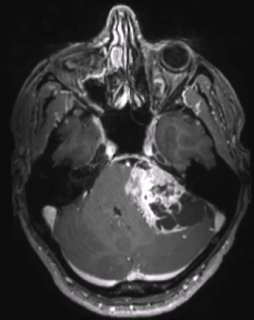

интересный случай! И не менее интересны ваши мнения! Мужчина 74 года.